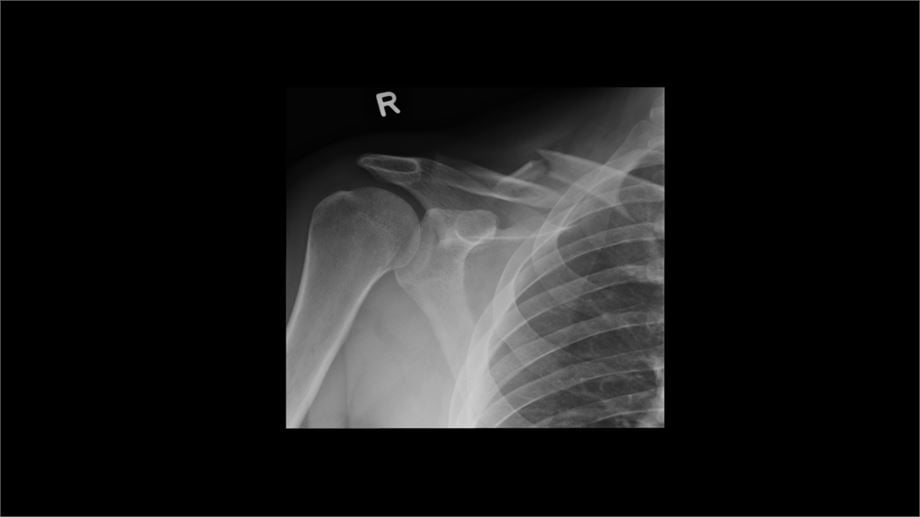

Tak wyglądał obojczyk zaraz po operacji: